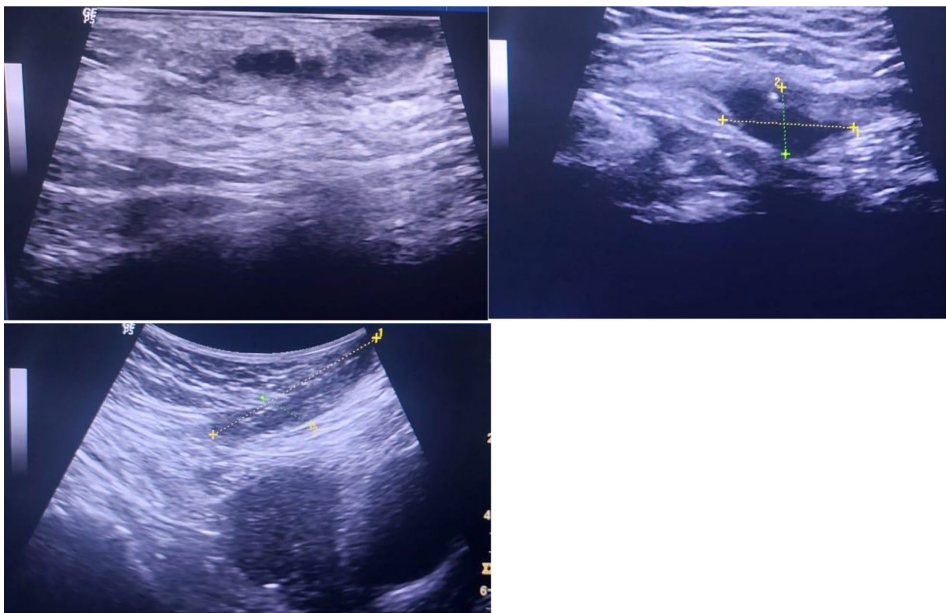

研究人员通过多模态影像学技术锁定了这个"逃亡者"的藏身之处。超声检查清晰显示出皮下混浊液性暗区中的IUD臂状结构(图2-3),同时盆腔X光片(图5)直观呈现了两个IUD的空间关系。最终通过精准的局部手术,这个引发慢性感染的"罪魁祸首"被成功取出(图6)。